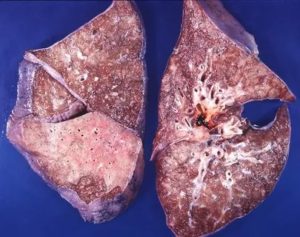

Морфологические признаки пневмонии представляют собой:

- очаги;

- крупозные участки.

Как выглядит пневмония на снимке (рентгеновском), если она крупозного вида:

- субтотальные, тотальные затемнения с одного или же двух краев;

- смещение средостения в сторону предельного поражения;

- изменение физического поражения куполов диафрагмы;

- закупорка реберно-диафрагмальных синусов жидкостью;

- полное деформирование легочного рисунка;

- тяжистость корней легких.

Выявить особенности крупозного воспаления возможно на рентгенограмме. Однако при патологии медицинским стандартом диагностики считается рентгенография в двух проекциях (прямая и боковая). Такого рода список процедур совершают для оценки численности пораженных частей легких и исследования состояния средостения.

Данной форме характерно формирование больших участков поражения легочной ткани. Патологический процесс может охватывать как одно, так и оба легких. На иллюстрации ниже показана тяжелая форма крупозной пневмонии.

При слиянии отдельных очагов воспаления легочной ткани возникает крупозная пневмония. Фото рентгеновского снимка, сделанного при этой форме заболевания, наглядно показывает отличия.

Как правило, при крупозной форме воспаления легких поражается одна или несколько долей легких сразу. Это создает серьезную угрозу жизни пациента.

На рентгене крупозная форма болезни проявляется следующими признаками:

- Ярко выраженные крупные тени, затрагивающие доли легкого целиком. Могут быть поражены оба легкого.

- Средостение смещается в сторону наиболее воспаленного легкого.

- На куполах диафрагмы отчетливо видны признаки деформации.

- Рисунок легочной ткани может не просматриваться.

Крупозная пневмония легче всего выявляется при рентгенологическом исследовании. Тем не менее для постановки точного диагноза врачи предпочитают делать рентгеновские снимки в двух проекциях. Это дает им возможность определить число пораженных воспалением сегментов органа и определить состояние средостения.